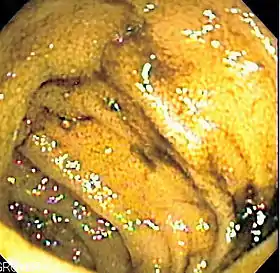

![]() Endoscopic image of normal small bowel | |